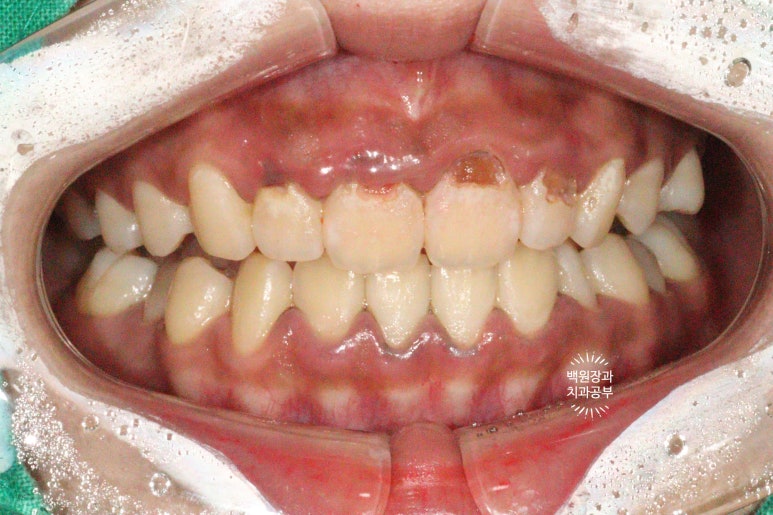

아주 시크하게 스케일링을 받으러 왔던 20대 여자 환자입니다.

개원 초반에 내원하셨었는데, 사진 퀄리티가 좀 좋지 않네요..!..

딱 봐도 잇몸이 부어 있으신 상태였습니다. 흡연자로써 치은연하치석 (잇몸 아래에 위치한 치석)이 많아 치주질환이 심하였고, 더불어 치태 관리가 되지 않아 충치도 여러군데 있었어요... 젊은 분이셨는데..